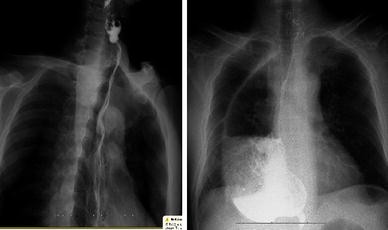

Barium esophagram showed that the constructed gastric tube was limited in the posterior mediastinum 6 months after LTE (left), while it might expand in the right plural cavity 6 months after CTLE (right)